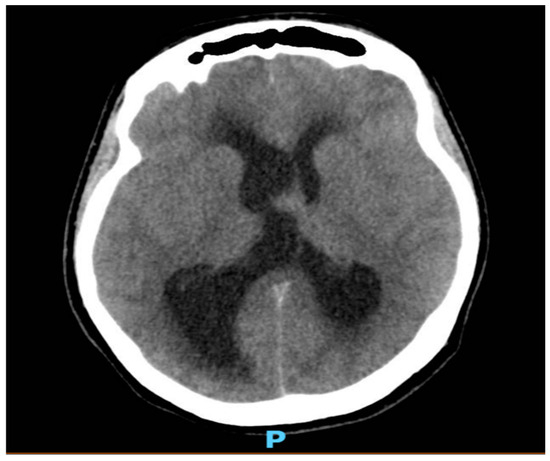

As shown in Figure 1 and Figure 2, neuroimaging with a head CT scan revealed a crucial finding: a colloid cyst situated at the roof of the third ventricle. This strategically located cyst was obstructing the normal flow of the cerebrospinal fluid (CSF), leading to obstructive hydrocephalus. Given the urgency of the situation, a prompt neurosurgical consultation was arranged.

Figure 1. A nonenhanced CT image of the brain showing an oval dense lesion at the roof of third ventricle measuring 1.7 × 1.6 cm, obstructing the foramen of Monro.